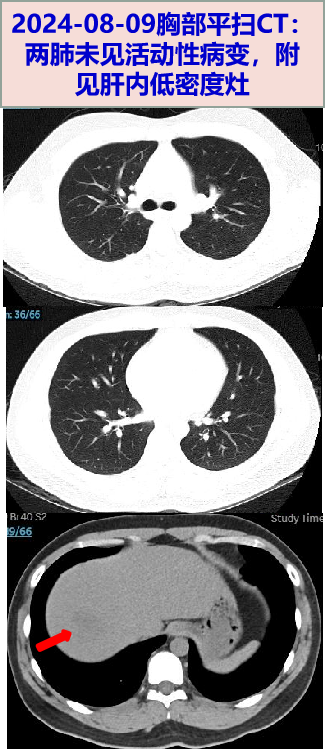

现病史

• 2024-08-05 无诱因下出现发热,Tmax 40℃,伴畏寒寒战、头晕头痛,呕吐胃内容物1次。08-09就诊我院门诊,查WBC 18.9×109/L,N 81.9%;CRP 185mg/L;新冠、甲乙流、呼吸道合胞病毒、腺病毒、鼻病毒、肺炎支原体核酸均阴性。胸部CT平扫:未见活动性病变,附见肝右叶低密度灶。颅脑CT平扫未见异常。予左氧氟沙星0.5g抗感染,寒战高热无好转。

• 2024-08-10 仍有寒战高热,Tmax 40.5℃。至我院门诊复诊,查WBC 15.2×109/L,N 81.9%;CRP 238.5mg/L,PCT 0.74ng/L;TB/DB 28.9/10.5μmol/L,ALT/AST 36/34U/L;D-二聚体 0.35mg/L。腹盆增强CT:肝脓肿,脂肪肝。肝脏B超: 肝右叶混合性占位,大小43*38mm—考虑脓肿形成可能。建议住院,患者拒绝。当日至急诊,考虑细菌性肝脓肿,予厄他培南 1g qd抗感染;介入B超下行经皮肝脓肿穿刺引流术,术中引流出脓血性液体(具体量不详)。08-10夜间出现剧烈呕吐1次,为胃内容物。

病史特点:青年男性,既往无慢性疾病基础,急性病程,发热伴恶心呕吐、头晕头痛1周余,WBC、CRP、PCT明显升高,入院前8月9日胸部CT及8月10日腹部CT:未见活动性病灶,腹部增强CT见肝脓肿,介入超声下肝脓肿穿刺引流出血性脓液,肝脓肿临床诊断明确,需进一步明确病原学诊断,继续抗感染治疗。追问病史,08-10夜间出现的呕吐较剧烈,为胃内容物,量较多,约500ml,伴呛咳,考虑呕吐后有误吸,出现明显低氧血症,8月13日肺动脉CTA发现,两下肺动脉分支远端充盈欠均、两肺炎症、两侧少量胸腔积液伴两肺部分不张,肺部病变的原因,考虑如下:

1. 社区获得性肺炎(CAP):患者急性起病,胸部CT显示两肺炎症,应考虑CAP,常见病原体包括肺炎链球菌、肺炎支原体、呼吸道病毒等,但该患者8月9日和10日的胸部CT检查中两肺未见活动性病灶,在极短的3天时间,迅速出现并发展为两肺较广泛的炎症,不符合CAP的病程进展规律,故常见病原体引起CAP的可能性不大